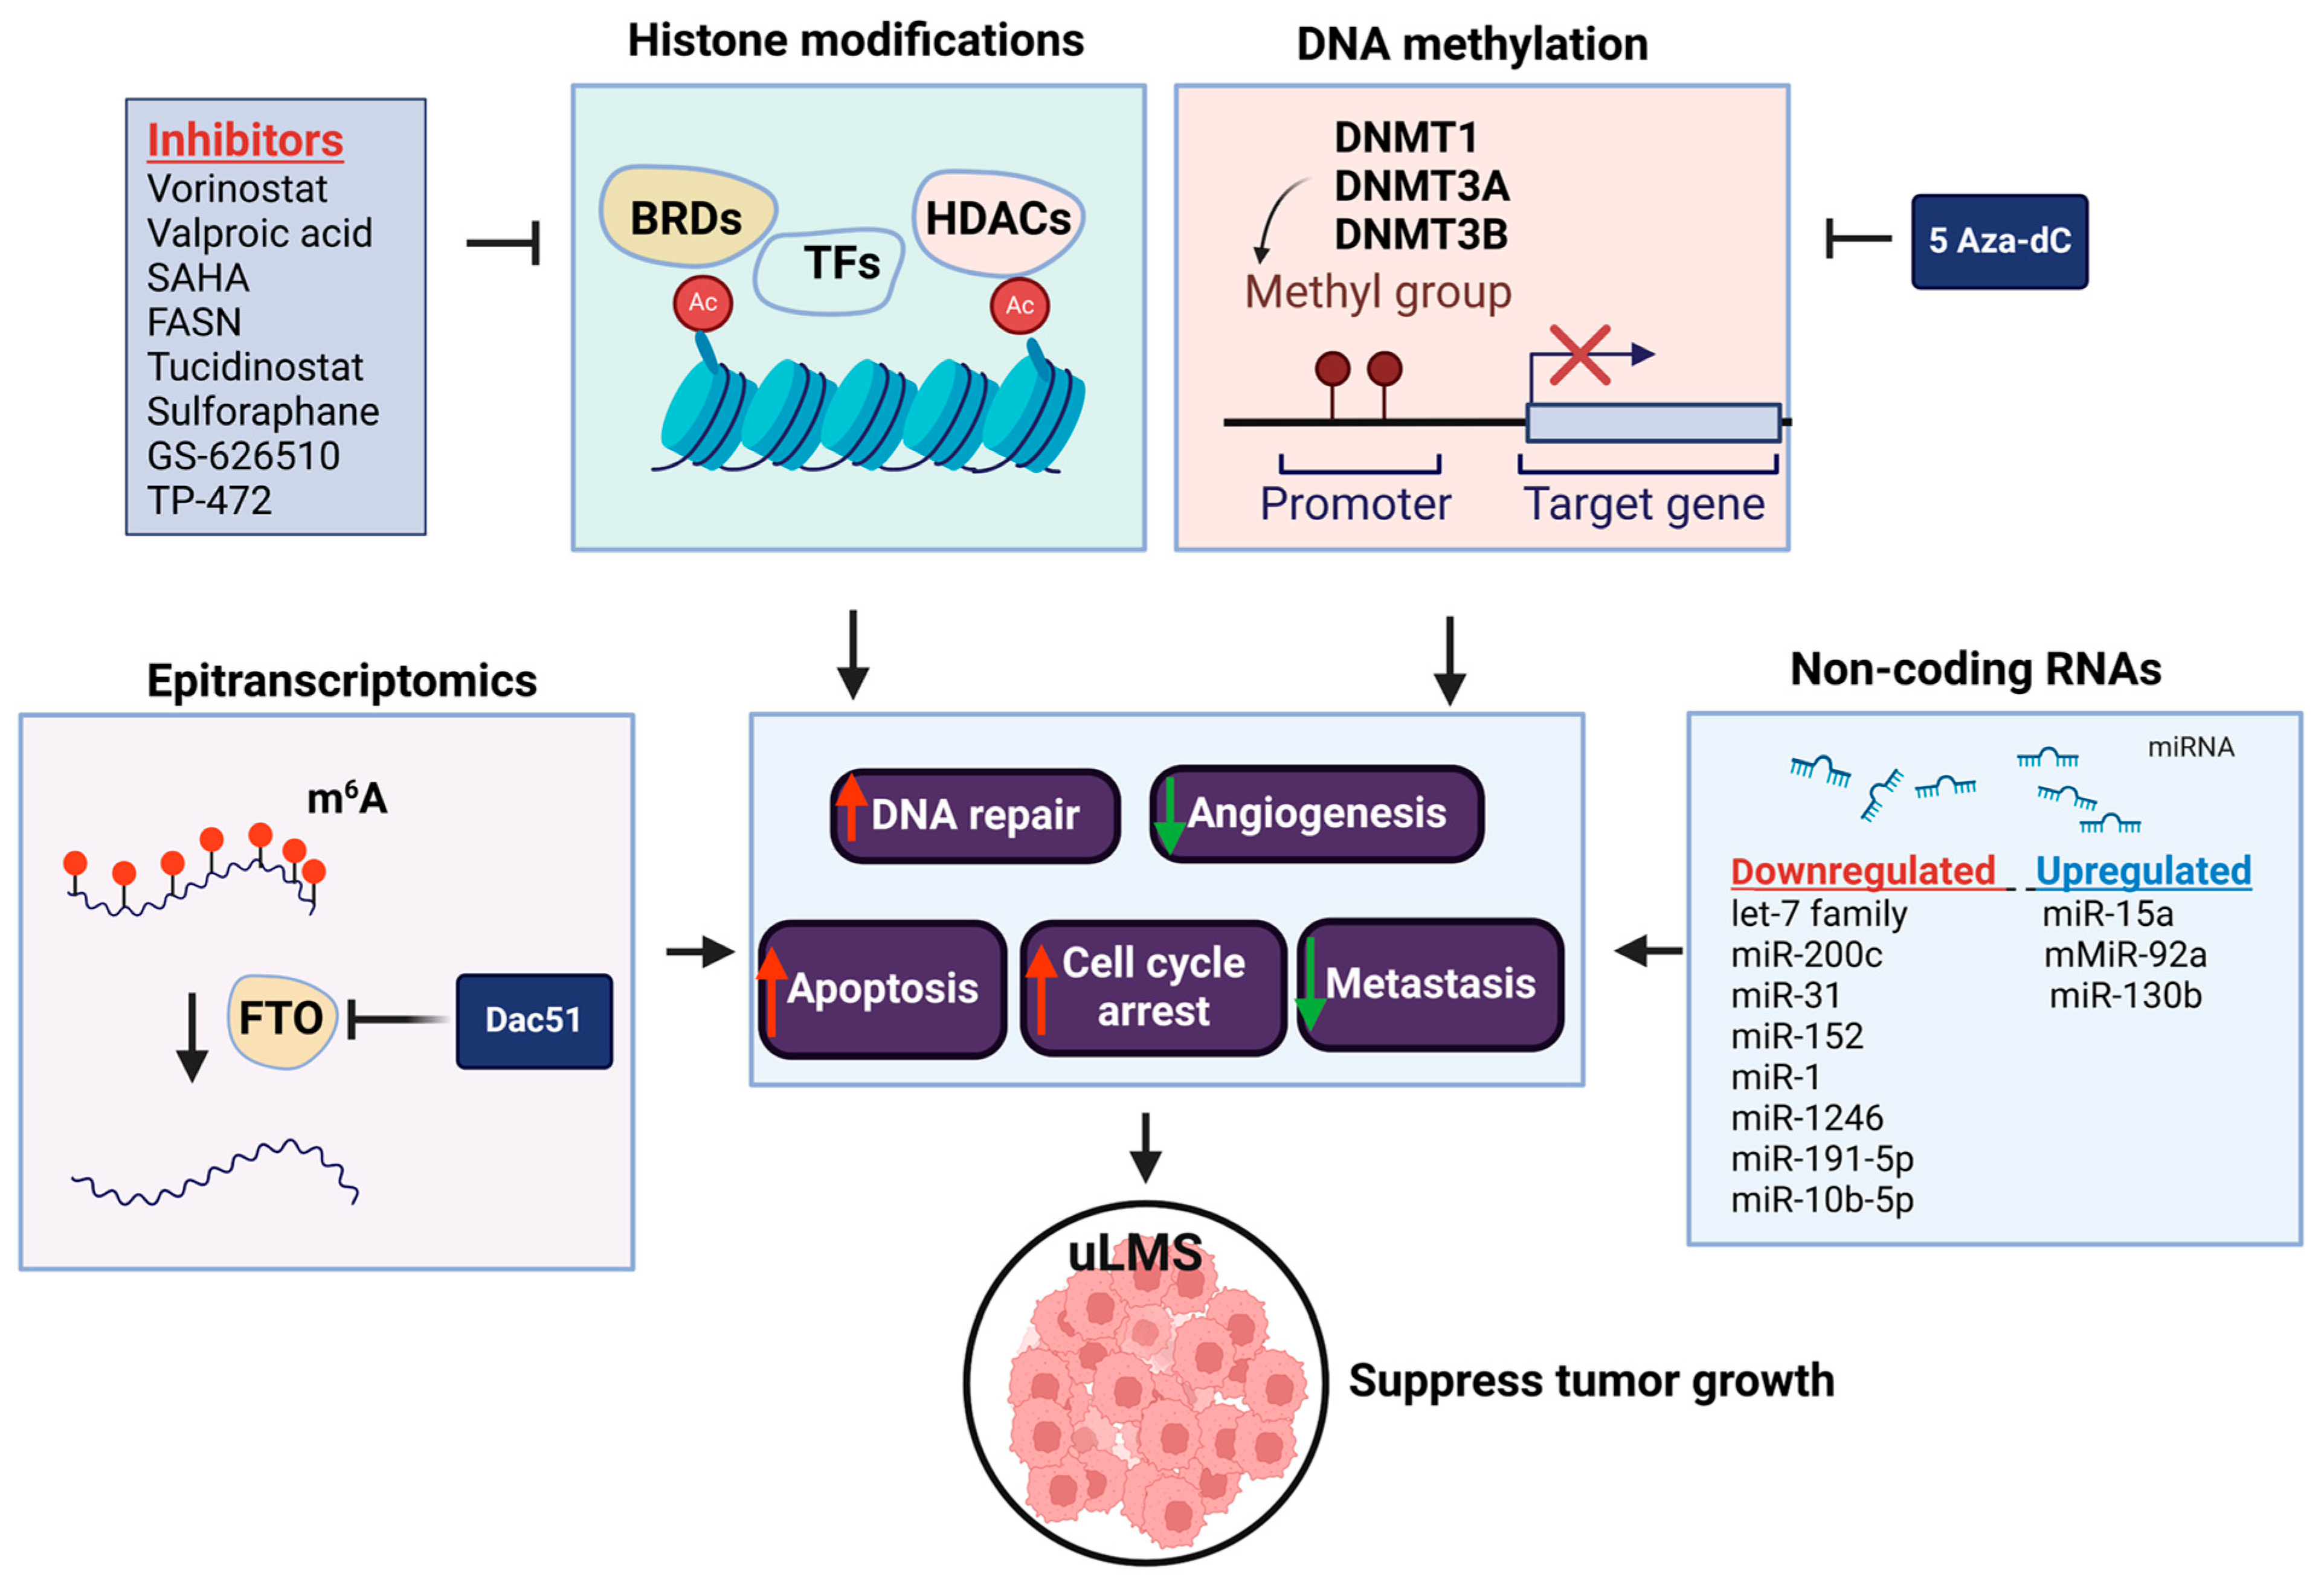

4. The Role of Epigenetics in the Pathogenesis of Leiomyosarcoma

4.1. DNA Methylation

4.2. Histone Modification

4.3. Non-Coding RNA

4.4. RNA Methylation